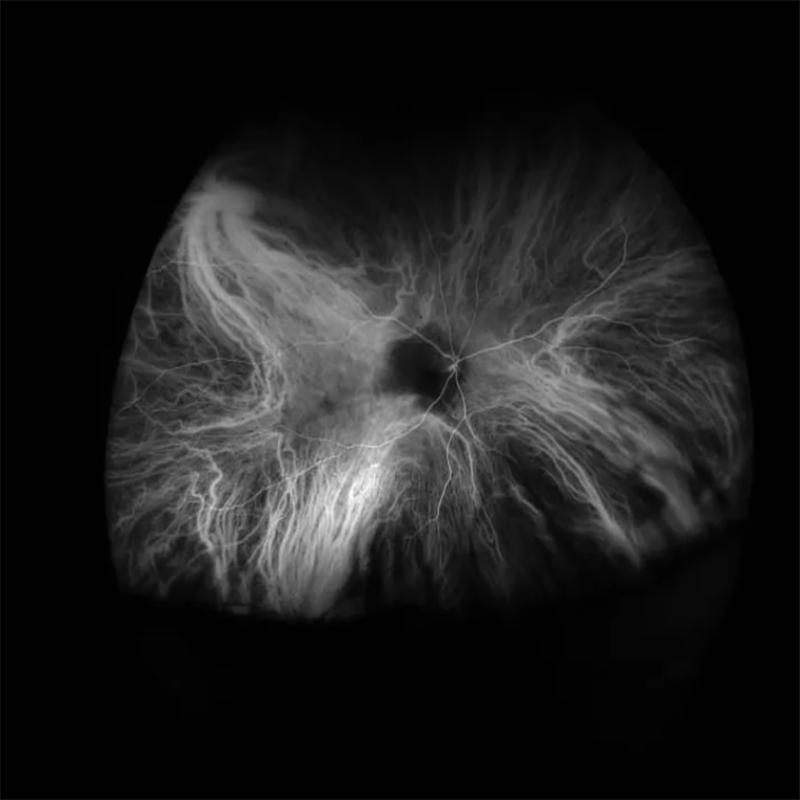

OPTOS SILVERSTONE SS OCT FLUORESCEIN ANGIOGRAPHY

Η υπέρ-ευρεία, υπερ-υψηλής ανάλυσης αγγειογραφία με φλουορεσκεΐνη του OPTOS SILVERSTONE SS OCT προσφέρει την ταυτόχρονη παρατήρηση ολόκληρου του αμφιβληστροειδούς χιτώνα του οφθαλμού.. Αυτό υποστηρίζει τους ιατρούς στη διάγνωση οφθαλμικής παθολογίας που ίσως παρουσιαστεί πρώτα στην περιφέρεια του αμφιβληστροειδούς, με αποτέλεσμα πιο ακριβής διάγνωση για τον ασθενή.

Αυτό επιτρέπει την απεικόνιση ολόκληρου του αμφιβληστροειδικού αγγειακού δικτύου κατά την έγχυση της χρωστικής μέσω ανέπαφης μεθόδου